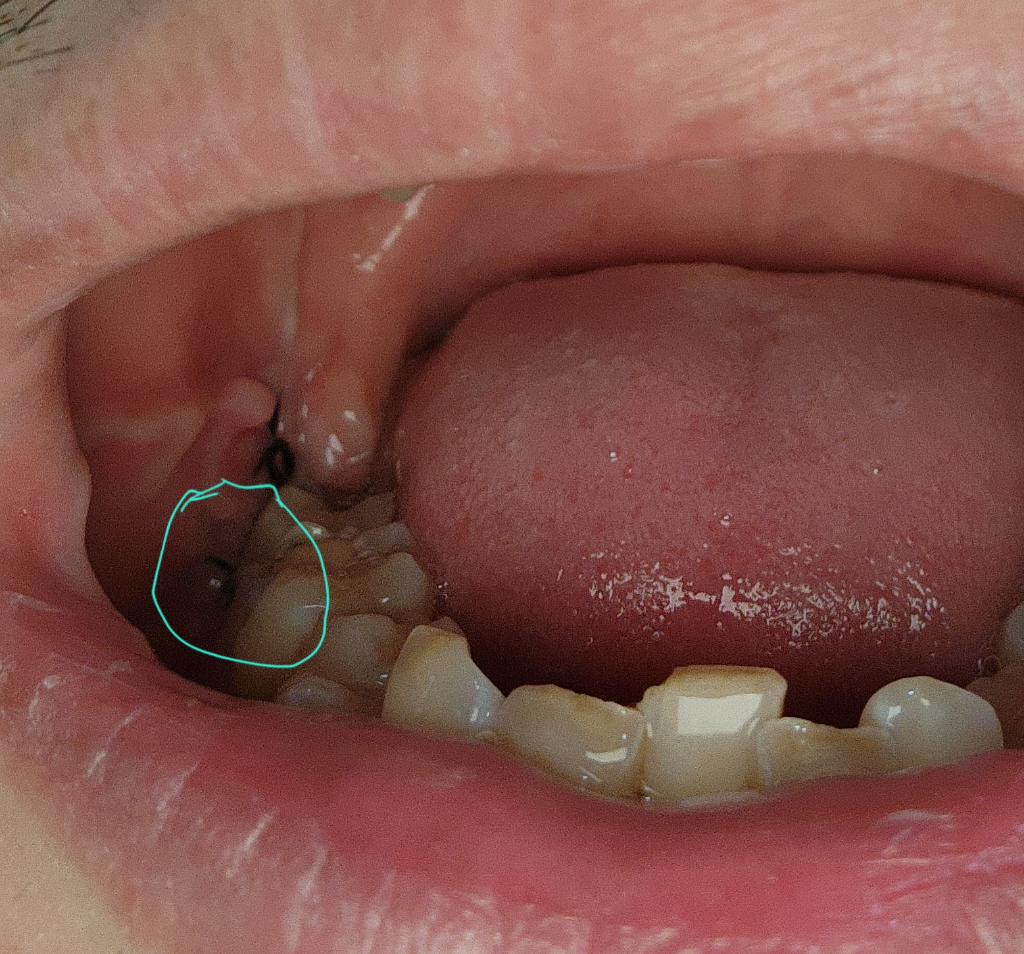

매복사랑니 7일치입니다 질문드릴게요

저기 동그라미 친부분이 옆어금니 절개로해서 뒤쪽까지 절개해서 매복사랑니 뺏는데요 옆어금니쪽 절개한 부분에 지금 하얀게 올라와 잇고요 그사이에 조금만한 구멍이 생겻는데 밥먹을 때만 통증 잇고 평상시에는 통증 없고 진통제 안먹고 잇는데 저기 절개한 밥한톨사이즈 들어갈것 같은 구멍 신경안써도 되나요 어제 치과갓는데 보더니 잘 아물고 잇다는데 구멍이 신경스이네요 잘못된거 아니겟죠?

• 1번 째 사진

저정도는 시간이 지나면서 자연스럽게 아물게 됩니다. 실밥을 풀고나서 양치만 잘하시면되니 너무 걱정하지마세요.

구멍은 자연스럽게 닫힐 겁니다. 아직 일주일 밖에 되지 않으셨으니 주의사항 잘지키면서 기다리시면 됩ㄴ디ㅏ.

사랑내를 발치하게 되면 해당 부위에 상처가 생길 수 있습니다. 생긴 구멍은 시간이 지나면서 줄어들게 되며 발치 한 부위를 자극하지 않는 것이 좋습니다